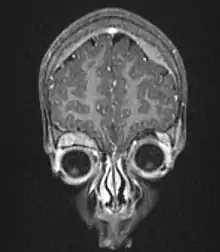

Another way to detect neuroblastoma is the meta-iodobenzylguanidine scan, which is taken up by 90 to 95% of all neuroblastomas, often termed "mIBG-avid".[25] The mechanism is that mIBG is taken up by sympathetic neurons, and is a functioning analog of the neurotransmitter norepinephrine. When it is radio-iodinated with I-131 or I-123 (radioactive iodine isotopes), it is a very good radiopharmaceutical for diagnosis and monitoring of response to treatment for this disease. With a half-life of 13 hours, I-123 is the preferred isotope for imaging sensitivity and quality. I-131 has a half-life of 8 days and at higher doses is an effective therapy as targeted radiation against relapsed and refractory neuroblastoma.[26] As mIBG is not always taken up by neuroblastomas, researchers have explored in children with neuroblastoma whether another type of nuclear imaging, fluoro-deoxy-glucose – positron emission tomography, often termed "F-FDG-PET", might be useful.[27] Evidence suggests that this might be advisable to use in children with neuroblastoma for which mIBG does not work, but more research is needed in this area.[27]